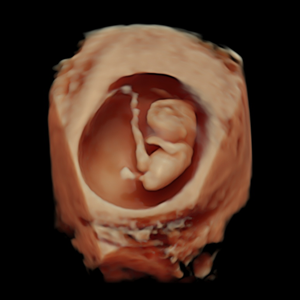

- Pionero en México en ofrecer diagnóstico por ultrasonido dentro del consultorio, así como en incorporar tecnología 3D y Doppler.